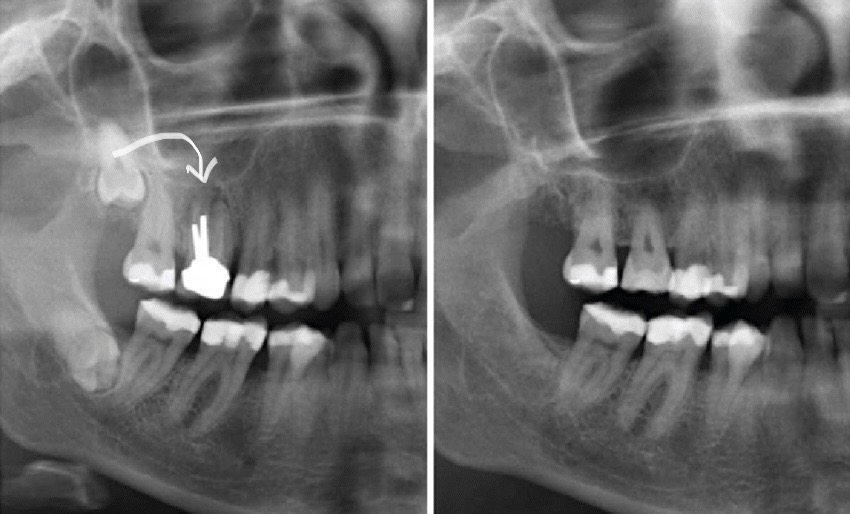

Diş autotransplantasiya, diş həkimliyi sahəsində geniş yayılmış bir cərrahi prosedurdur. Bu prosedur, bir dişin bir bölgədən götürülüb başqa bir bölgəyə yerləşdirilməsini əhatə edir. Əsasən, çürük, travma və ya digər səbəblərlə itirilmiş bir dişin yenisi ilə əvəz edilməsi məqsədilə tətbiq olunur. Autotransplantasiya zamanı uğurlu nəticə əldə etmək üçün adətən köçürüləcək dişlərdə köklərin tam formalaşmamış olmasına diqqət yetirilir. Bu baxımdan bu müalicə metodu daha çox uşaqlarda və gənclərdə daha çox uğurla tətbiq edilir.

Bu prosedur, xəstənin öz dişindən istifadə edilərək həyata keçirildiyi üçün orqanizmin rədd etmə riski mövcud deyil. Amma, uğurlu nəticə üçün diqqətli bir cərrahi texnika və uyğun xəstə seçimi vacibdir. Bundan başqa, köçürülən dişin tutması və funksionallığını qorumaq üçün uyğun baxım və izləmə vacibdir.